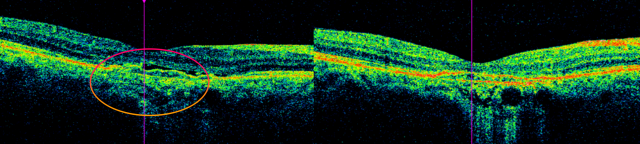

습성황반변성은 눈 주사제, 레이저 치료 등으로 치료한다. 습성의 경우 과거에는 거의 치료가 불가능했지만, 최근 루센티스, 아일리아 등 효과가 입증된 눈 주사제가 속속 도입돼 환자의 시력을 보존할 수 있게 됐다. 65세 A 씨의 경우 부산의료원에서 한 달 간격으로 3회 주사 치료를 받은 뒤 망막하액(망막 아래 물이 찬 것)이 없어지고 물체가 찌그러져보이는 증상도 사라졌다. 이후 3개월마다 주사 치료를 받고 있다.

65세 A 씨는 시력이 저하되고 물체가 가끔 찌그러져보이는 증상으로 부산의료원을 찾아 주사 치료를 받았다. 빛간섭단층촬영에서 망막하액(원 안)이 관찰된 모습과 3차례 주사 치료 후 망막하액이 사라진 모습(오른쪽). 부산의료원 제공 65세 A 씨는 시력이 저하되고 물체가 가끔 찌그러져보이는 증상으로 부산의료원을 찾아 주사 치료를 받았다. 빛간섭단층촬영에서 망막하액(원 안)이 관찰된 모습과 3차례 주사 치료 후 망막하액이 사라진 모습(오른쪽). 부산의료원 제공